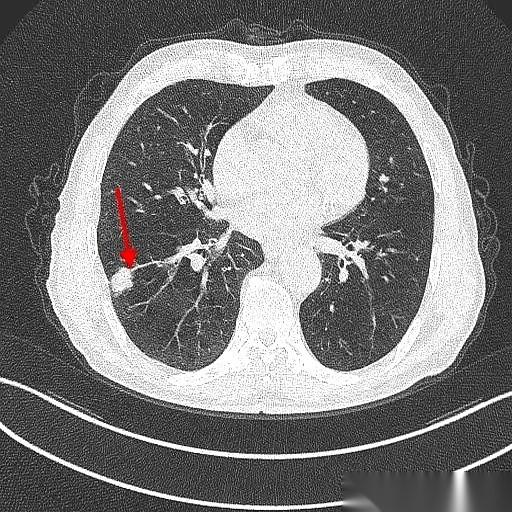

肺鳞癌,手术切完9年了,人活得好好的。 最绝的是,这大爷手术后烟都没戒。 真的,就是少抽了点。 说起来也邪门,当初救了他一命的,竟然就是他那要命的咳嗽和胸闷。要不是这俩症状把他折腾得受不了,跑去医院拍了个片子,那个藏在肺里2.4厘米的坏东西,还不知道要逍遥到什么时候。 一个抽了40年烟的71岁老爷子,你想想那犟劲儿。 手术很成功,切下来一看,万幸,早期,淋巴也没事。按理说,这都鬼门关前走一遭了,总该惜命了吧? 人家偏不。 就这么吊儿郎当地,九年过去了。 每年复查,啥事没有,肿瘤连个鬼影都见不着。有时候你真的会怀疑,老天爷是不是也有自己的KPI,专门考核戏剧性。 但命运这东西,总爱在结尾给你来个回马枪。 癌是没了,肺气肿倒是越来越厉害了。CT片子上,那肺啊,被烟熏得千疮百孔的。 老爷子今年终于又提了,说,准备戒烟。 也不知道这次是不是真的。 你说这人啊,有时候命硬得像块石头,有时候又犟得让人哭笑不得。 躲得过阎王爷,却好像总躲不过自己亲手点燃的那根烟。